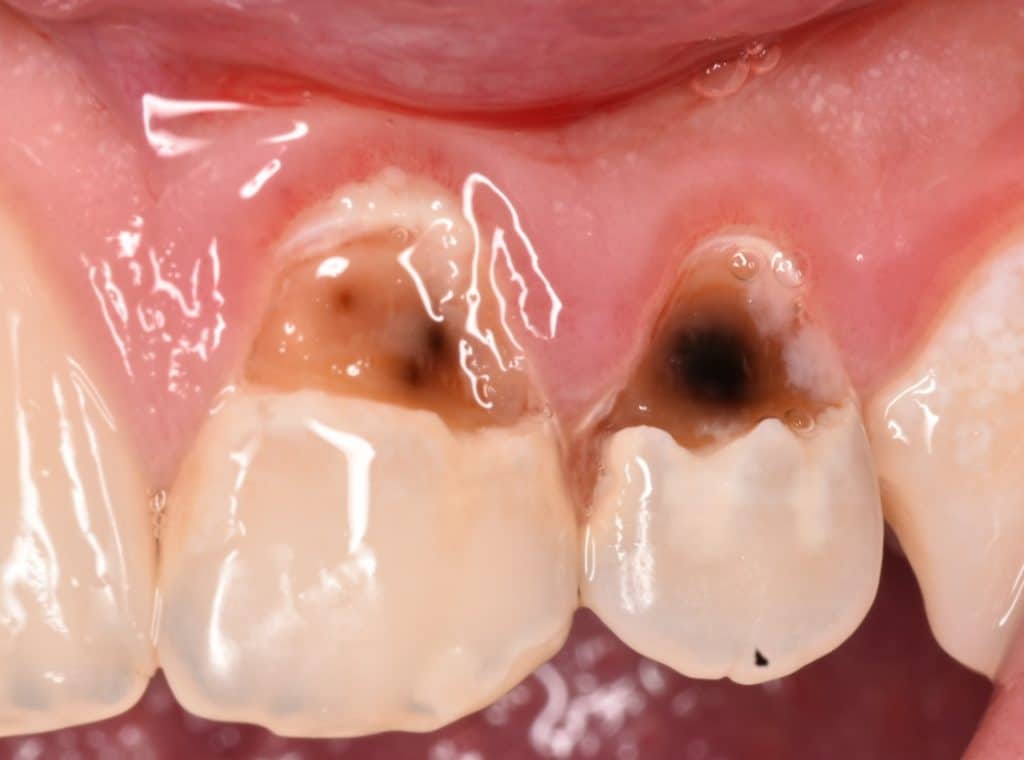

Direct anterior composite for 14 years old child

Initial situation showing large cervical caries in all his anterior teeth , I will take these 2 teeth as example the other teeth will posted in another post